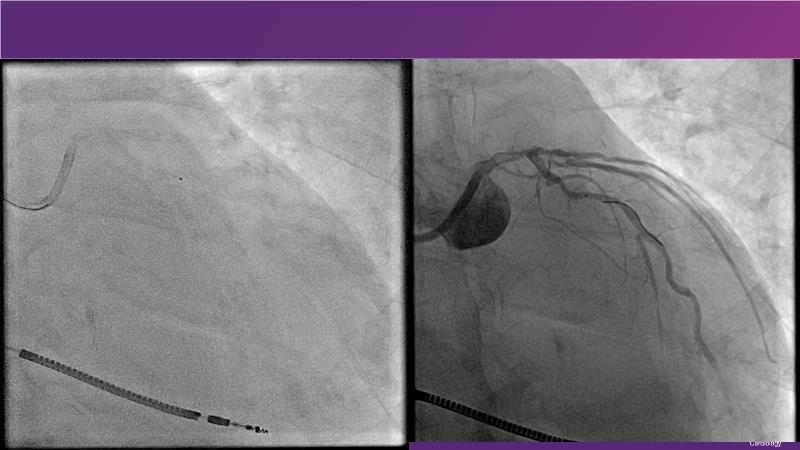

Cracking calcium: best practices to integrate intravascular lithotripsy into your calcium management algorithm

With this session, keep up to date on the evidence, trials and outcome data for intravascular lithotripsy in severely calcified lesions. Learn how to use this technique in real-world patients and understand its role in the treatment algorithm for severely calcified coronary lesions.

- To know the evidence, trials and outcome data for intravascular lithotripsy in severely calcified lesions